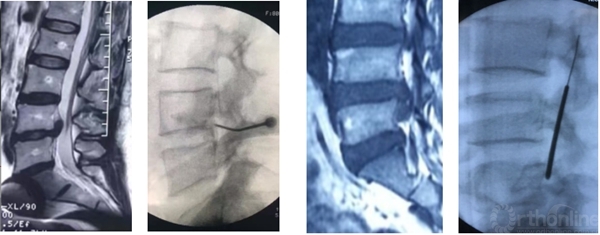

术前造影显示后纵韧带完整性,术中保护后纵韧带

脊柱内镜日间手术需进一步提高穿刺的精准性,避免反复穿刺。

靶向穿刺